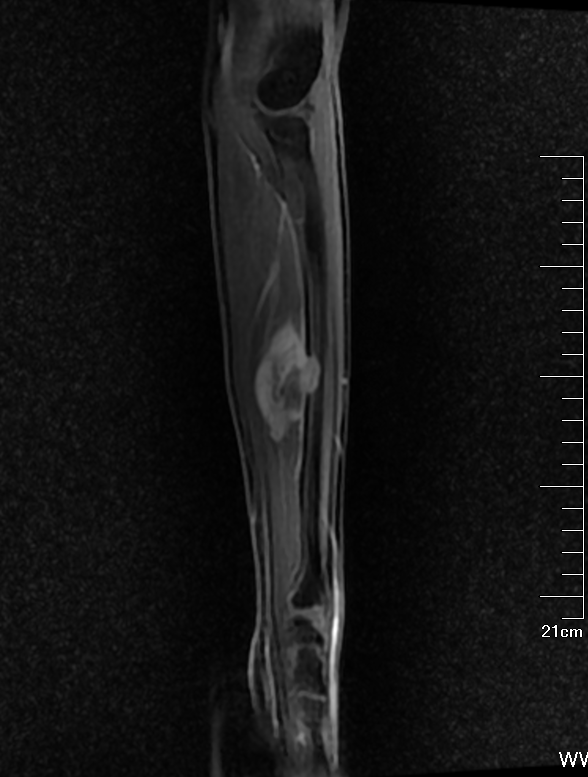

经过两个周期的化疗后,小贝的肿瘤由原来4.5cm*3.4cm缩小至3.0cm*2.8cm,在与家属沟通后,收治医院骨科准备行进一步治疗。小贝入院后,医院骨与软组织MDT(多学科联合会诊)团队针对病人病情进行研讨。综合评估远处脏器无转移,左前臂瘤灶缩小已有充足的外科边界进行保肢治疗。经专家团队讨论一直决定,对受肿瘤侵犯的组织进行整块切除,移植带血管蒂的自体腓骨重建尺骨缺损,肌腱成形重建伸肌和屈肌群功能。

▲ 新辅助化疗后复查MR